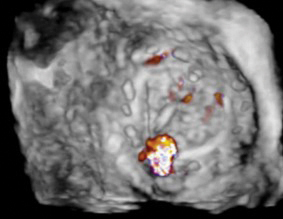

A stiff guidewire is advanced into the left ventricle, over which a 6-French coronary guide catheter is positioned. A 12-mm nitinol vascular plug is deployed across the defect, ensuring it straddles the PVL (see Fig. 6).

Fig. 6. Final short axis view of the mitral valve using 3D echocardiography. The image represents the view from the left atrium. The vascular plug (white arrow), deployed at the 6 o’clock position, now occupies the defect demonstrated in the short axis view of Fig. 4.